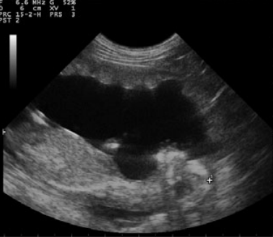

冠臀长通常被认为是可靠的脚气测定法中的参数。测量应为从牙冠(头骨的***上部)取到的臀部(结束的ac骨)(图1和2)什么时候的胎儿完全伸展。GA和CRL之间的高度相关性在不同品种的***个和第三个中期。CRL是确定GA的可靠参数(r=0.99)早怀孕。得出了一个新公式,发现是确定GA的方法非常准确:y=24:42+0:39X其中Y=胎龄,X=CRL。但是,无法执行此测量随着怀孕的进行准确;较低的错误高山山羊胎儿有相关系数的报道在妊娠第33天至146天之间。

图2 胎儿上冠状臀围长度的超声图像妊娠55天